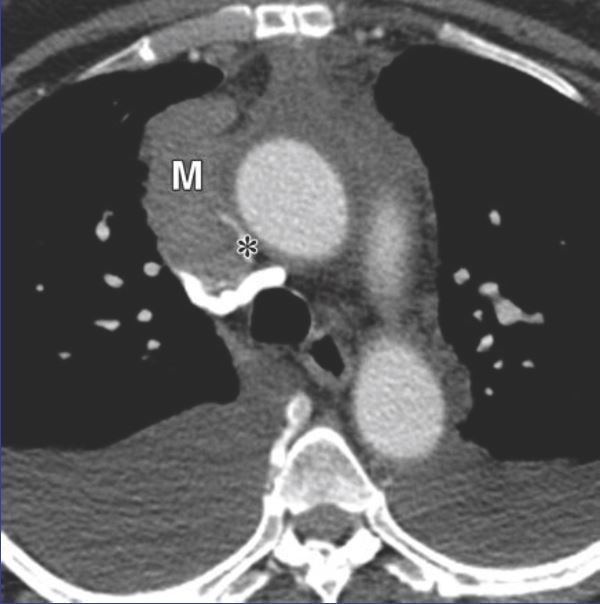

7.谢大夫,这个纵隔占位,是胸腺瘤吗?

回答:这是一个支气管囊肿,不是胸腺瘤,但有时候纵隔囊肿包括,胸腺囊肿,支气管囊肿,心包囊肿,术前很难鉴别诊断,有时即使CT结合磁共振也难以诊断。胸腺瘤往往也会合并胸腺囊肿,因此有时对于胸腺瘤和纵隔囊肿无法鉴别的情况下,必要时还是需要手术探查,依靠病理最终诊断。